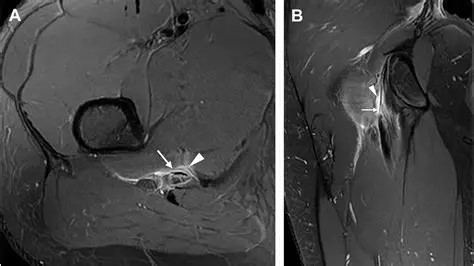

Imaging may include plain Xray, ultrasound or MRI. Xray is a useful test to assess for degenerative hip or sacroiliac disease, pelvic stress fracture or unexpected nasty pathology. Ultrasound can demonstrate thickening or calcification of the proximal hamstring tendon, but does lack accuracy when compared to MRI. MRI is much better at demonstrating tendonopathy with associated partial tearing. It can also assess for other soft tissue abnormalities such as ischiofemoral impingement. The scan will also address possible bone or joint pathology such as a sacral or pelvic stress fracture or hip or SIJ degenerative change.